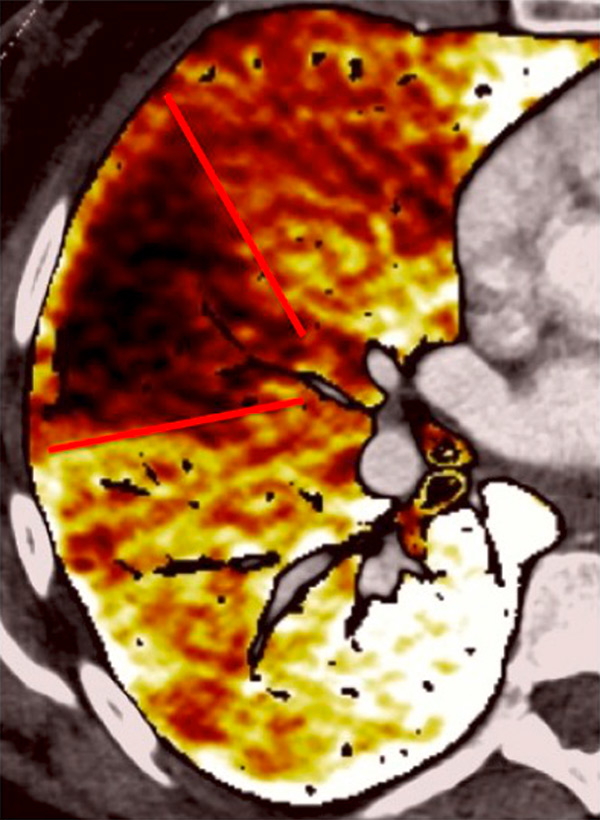

Figure 10

Severe bronchopathy (arrow) in the left lower lobe (A) associated with extended hypoperfusion (arrow) and dilatation of the right cardiac cavities (stars) (B).